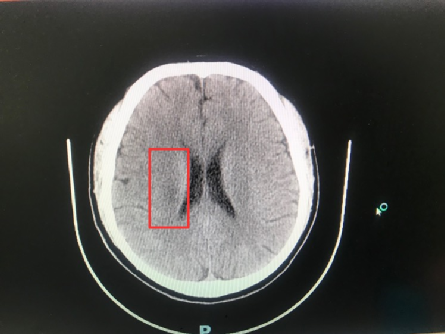

回宁后不久,黄先生再次出现左侧肢体无力的情况,且症状较首次发病时更明显,于是在家人的陪同下来到泰康仙林鼓楼医院就诊。复查头颅CT显示,黄先生的大脑组织缺血状态仍然存在。

右侧侧脑室旁纵行低密度影,提示低灌注性梗死